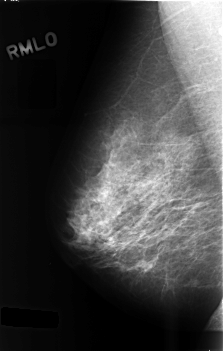

Digital Database for Screening Mammography

Volume: benign_13 Case: C-0487-1

C_0487_1.RIGHT_MLO

RIGHT_MLO LINES 4552 PIXELS_PER_LINE 2896 BITS_PER_PIXEL 12 RESOLUTION 50 NON_OVERLAY